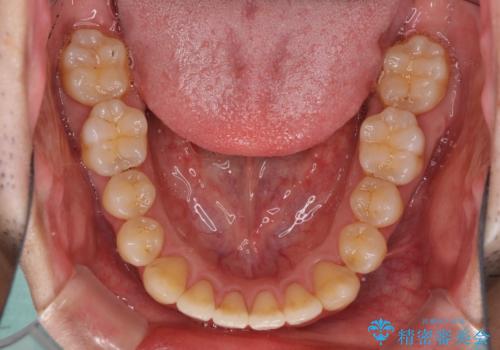

インビザラインによる反対咬合の改善は、上の歯が下の歯を乗り越えていく期間に咬み合わせが非常に不安定となり、治療が長期化することがあります。

また、ワイヤー矯正と異なり歯軸改善の強い力を前歯にかけるため、反対咬合で裏側にある歯の歯肉が退縮しやすくなります。

矯正治療により元々気になっていた八重歯と、反対咬合が改善された歯の2本に対して根面被覆を行い、審美面の改善も達成しました。